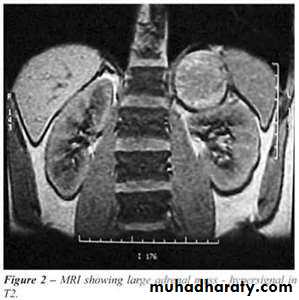

2- imaging study for the localization of the phaeochromocytoma and/or metastases. MRI is preferred because contrast media used for CT scans can provoke paroxysms.

3-MRI and CT are equally effective in distinguishing adrenocortical adenoma from carcinoma .

The adrenals are pair of glands of about 4 grams situated at the upper poles of kidneys in the retro peritoneum within Gerota’s capsule.